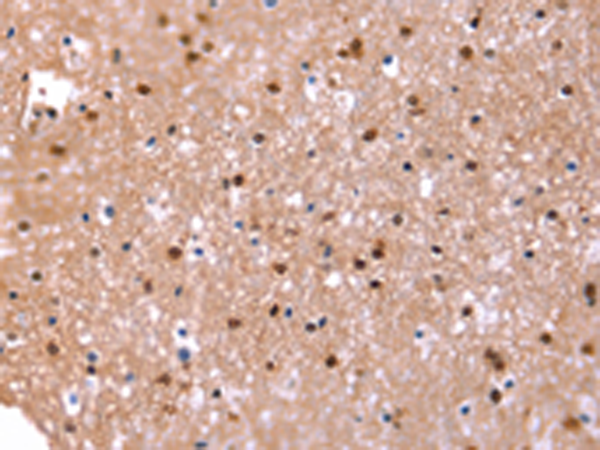

IHC positive control: |

Human brain |

IHC Recommend dilution: |

25-100 |